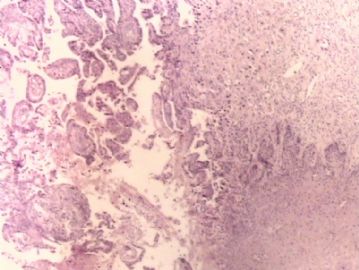

腺鳞癌?

姓    名: ××× 性别:   年龄:  39岁

标本名称:  宫颈活检

简要病史:  同房出血3次,tct HSIL

考虑:原位腺癌,小灶性区域有鳞状上皮向间质内浸润,考虑有鳞状细胞癌结构。